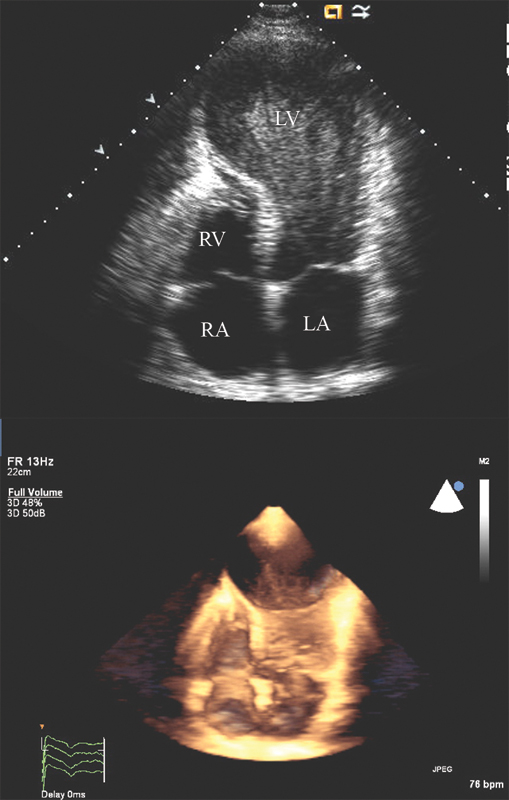

فحوصات تشخيصية لبعض امراض القلب والشرايين التاجية